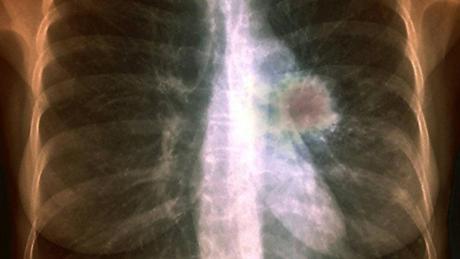

“Las células cancerosas tienen un metabolismo distinto al de las que están sanas, así que cuando hay crecimiento de cáncer en el tejido pulmonar de una persona se pueden detectar los productos de su metabolismo en el aliento”, aclaró.

Sin embargo, datos del Instituto Nacional de Salud Pública indican que en 2020 en México se registraron siete mil 811 casos de cáncer de pulmón y seis mil 733 muertes por esta causa.